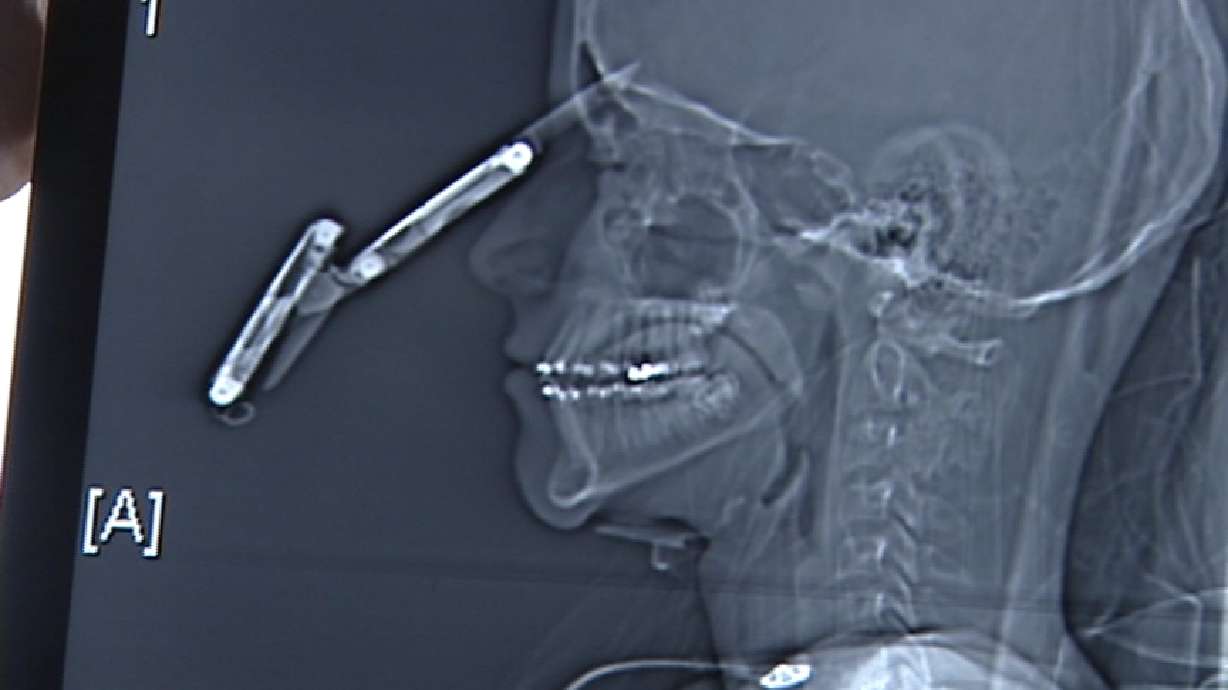

**Warning: This story contains a graphic image. If you do not wish to see this, stop reading now.**Tonya Papanikolas Reporting

The boy is doing remarkably well after surgery. While his story is incredible, we want to warn you, you are about to see some graphic images of the knife in his head.

The surgery, which included repairing Kevin's sinus cavity, took four hours. It turns out the knife was lodged between the two lobes of the brain.

Kevin Coulter: "They said it was two millimeters away from a major vessel in my brain."